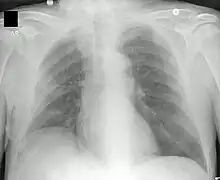

![]() Neumonía apical derecha: en la FQ, la infección crónica da lugar a la destrucción del parénquima pulmonar, ocasionando por último la muerte por insuficiencia respiratoria. | ||